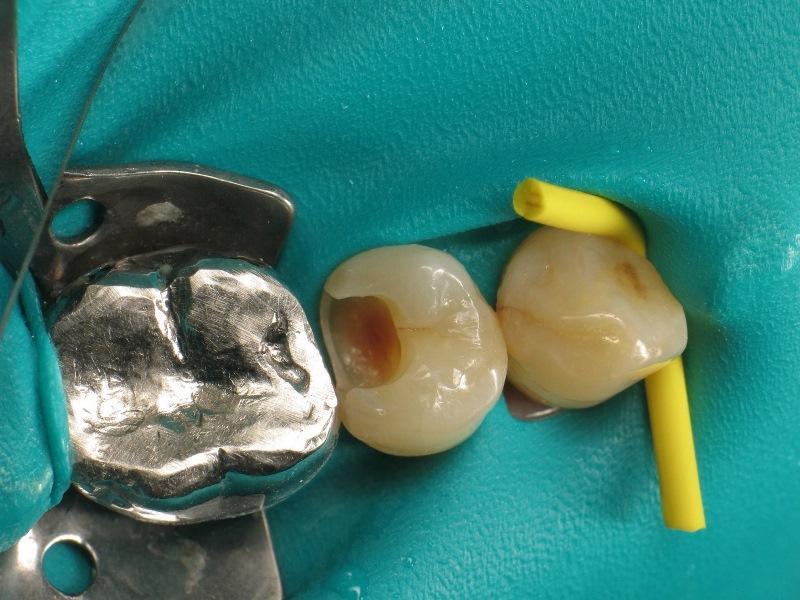

Фото 3: Полость после удаление кариозных тканей.